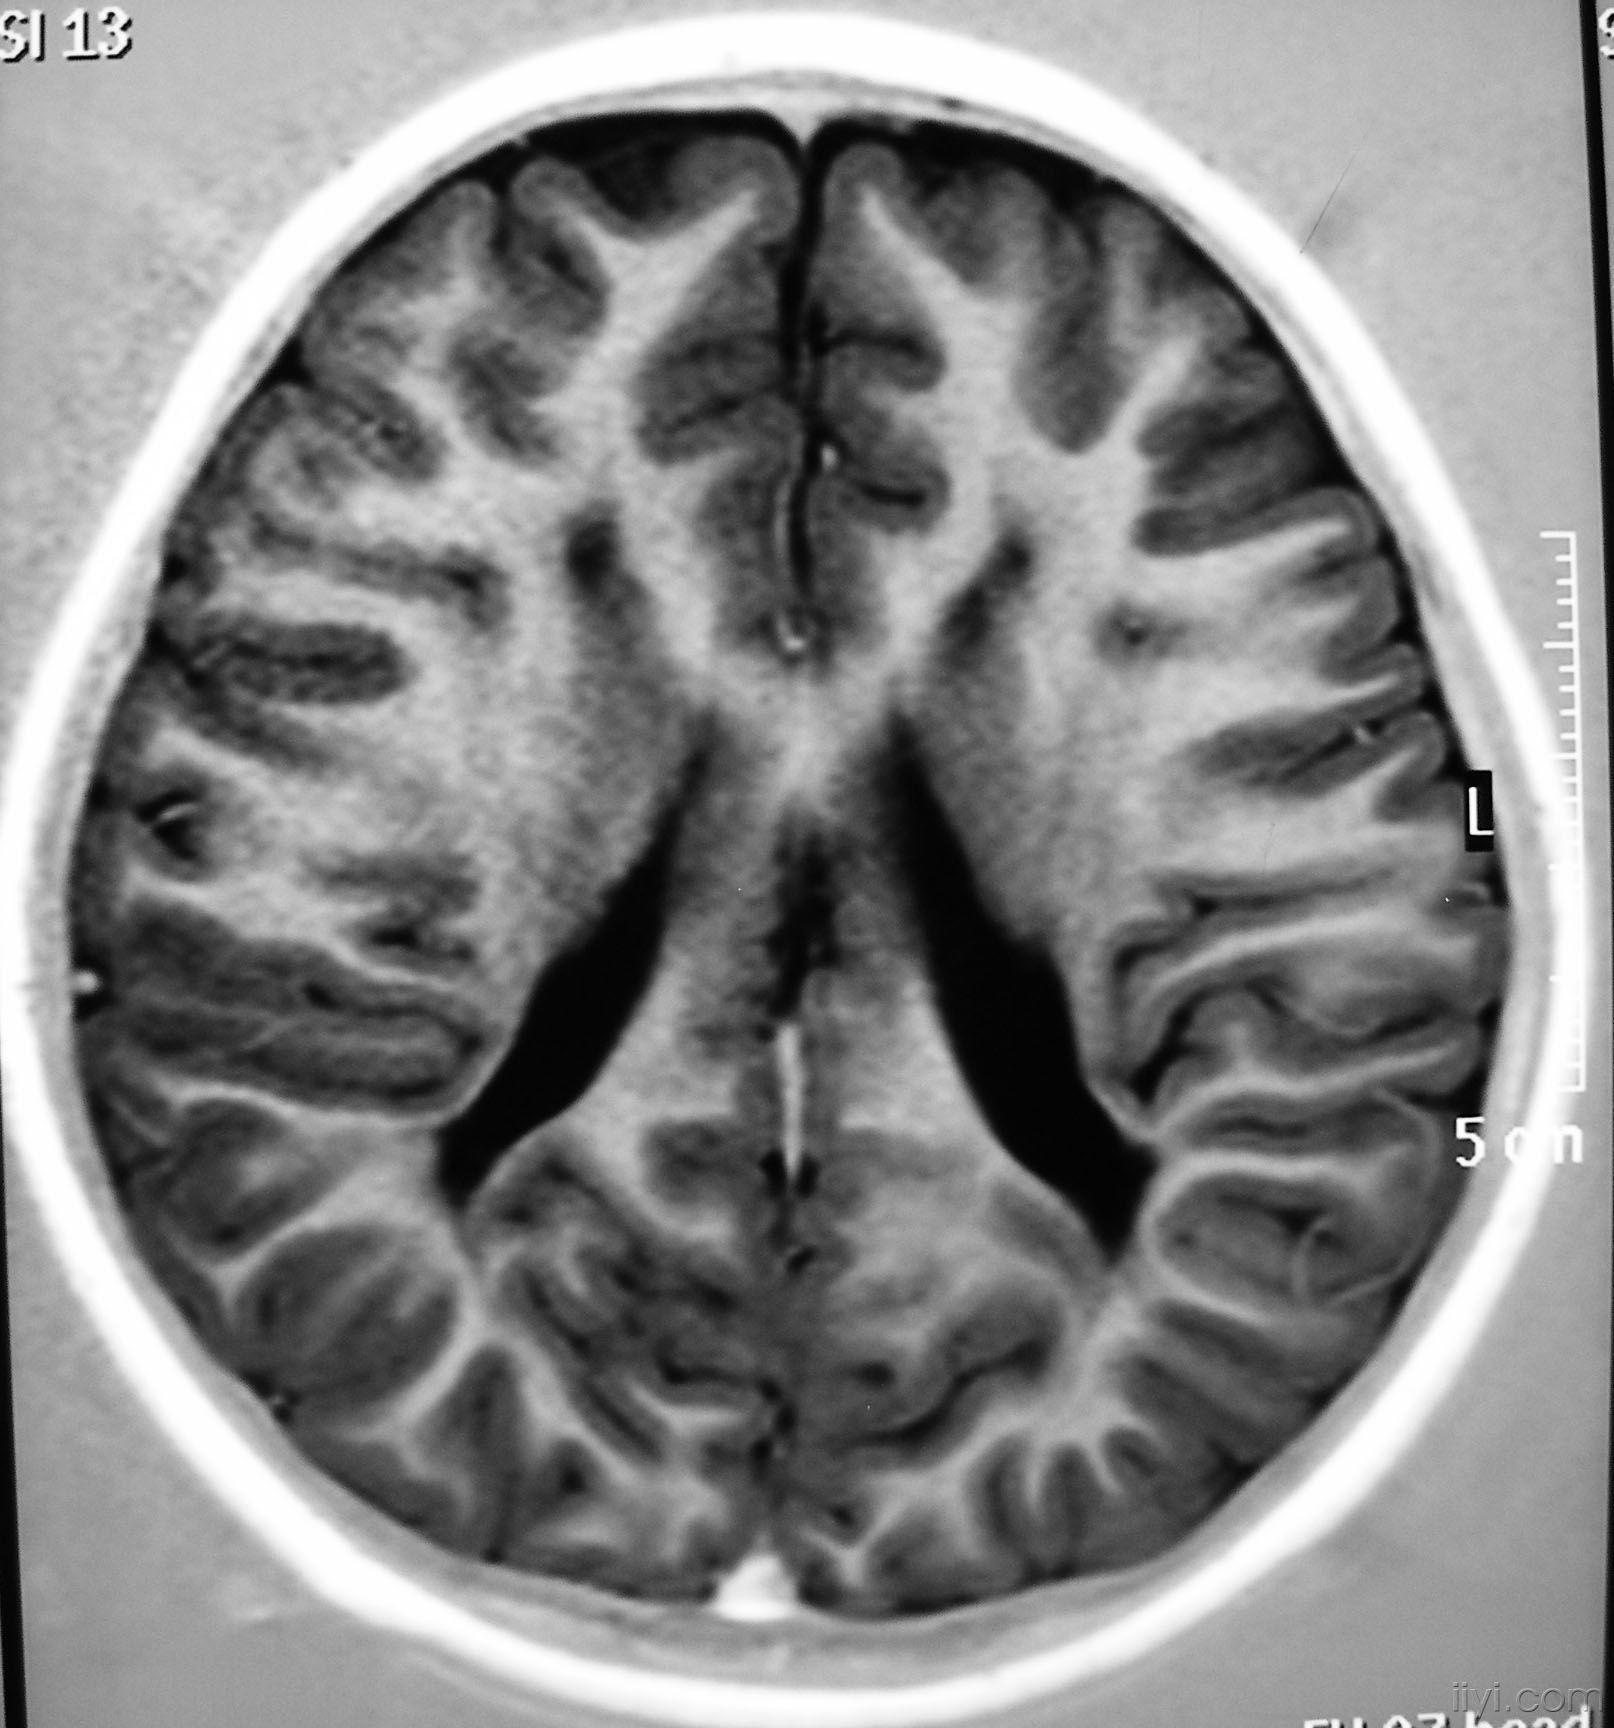

pvL

主要与脑缺血缺氧有关,多见于早产儿,是造成脑瘫的主要原因

影像学发生于侧脑室周围,侧脑室扩大,脑白质减少。扩大的侧脑室外缘常不规则为其特点,多为双侧脑室同时扩大。脑白质减少,脑皮层与脑室侧缘相近。MRI T1呈低信号,T2呈高信号。